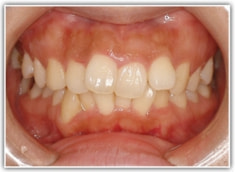

上顎前突ケース

治療法:表の矯正(T21ブラケット)

治療後(2年後)